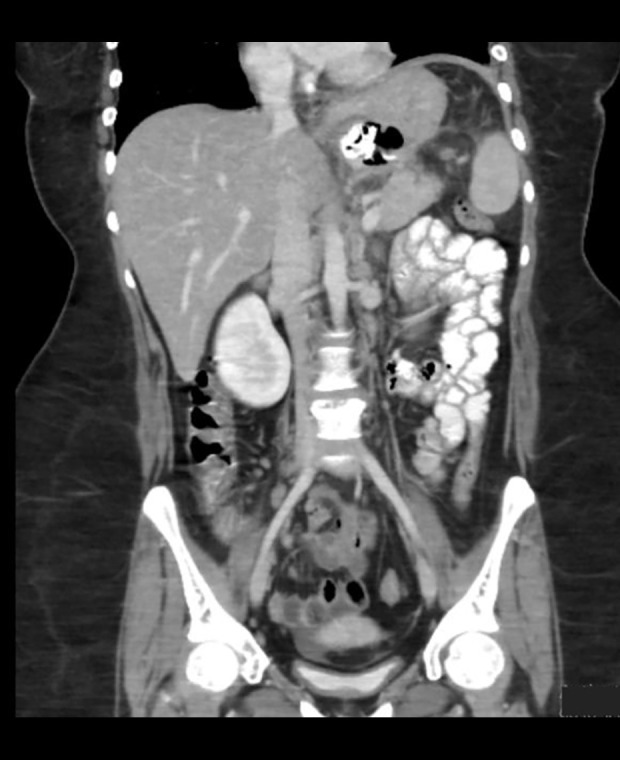

背景房间隔缺损(ASD)封堵器是治疗袖胃切除术后持续性胃漏的一种新方法。虽然袖式胃切除术是有效的,但初次手术的术后漏率高达3%,复诊时漏率超过10%,管理仍然复杂和不规范。病例报告:本病例报告描述了一名20岁的沙特妇女,她在腹腔镜袖胃切除术后发生胃漏。在最初的治疗失败后,自体扩张巨型支架的迁移,她提出了严重的症状和明显的包膜下脾集合。尽管超声引导引流和内镜干预,渗漏仍然存在。在修复失败后,使用内镜和透视引导部署ASD闭塞装置。虽然应用后成像最初未显示渗漏,患者病情有所改善,但后来患者出现持续渗漏的复发症状。该病例最终通过Roux-en-Y胃旁路手术得到解决。结论:本病例强调了ASD封堵器治疗复杂胃漏的潜力,特别是对于不愿重复手术的患者。该设备的重新定位和恢复的灵活性,结合内窥镜兼容性,使其成为治疗术后肥胖并发症的宝贵工具。虽然初步结果很有希望,但需要进一步的研究来验证这种方法的有效性和安全性。未来的研究应该集中在更大的队列上,以建立ASD设备在胃肠道应用的指导方针。

BACKGROUND Atrial septal defect (ASD) occluder devices present a novel approach for managing persistent gastric leaks following sleeve gastrectomy. While sleeve gastrectomy is effective, postoperative leak rates reach up to 3% in primary surgeries and exceed 10% in revisions, with management remaining complex and non-standardized. CASE REPORT This case report describes a 20-year-old Saudi woman who developed a gastric leak after laparoscopic sleeve gastrectomy. After a failed initial treatment with a self-expandable mega stent that migrated, she presented with severe symptoms and a significant sub-capsular splenic collection. Despite ultrasound-guided drainage and endoscopic interventions, leakage persisted. An ASD occluder device was deployed using endoscopic and fluoroscopic guidance following failed repairs. While post-application imaging initially showed no leaks and the patient's condition improved, she later experienced recurrent symptoms with persistent leakage. The case was ultimately resolved through a Roux-en-Y gastric bypass. CONCLUSIONS This case highlights the potential of ASD occluders in treating complex gastric leaks, particularly for patients reluctant to undergo repeated surgeries. The device's flexibility for repositioning and retrieval, combined with endoscopic compatibility, makes it a valuable tool for managing postoperative bariatric complications. While initial results are promising, further research is needed to validate this approach's efficacy and safety. Future studies should focus on larger cohorts to establish guidelines for ASD device use in gastrointestinal applications.